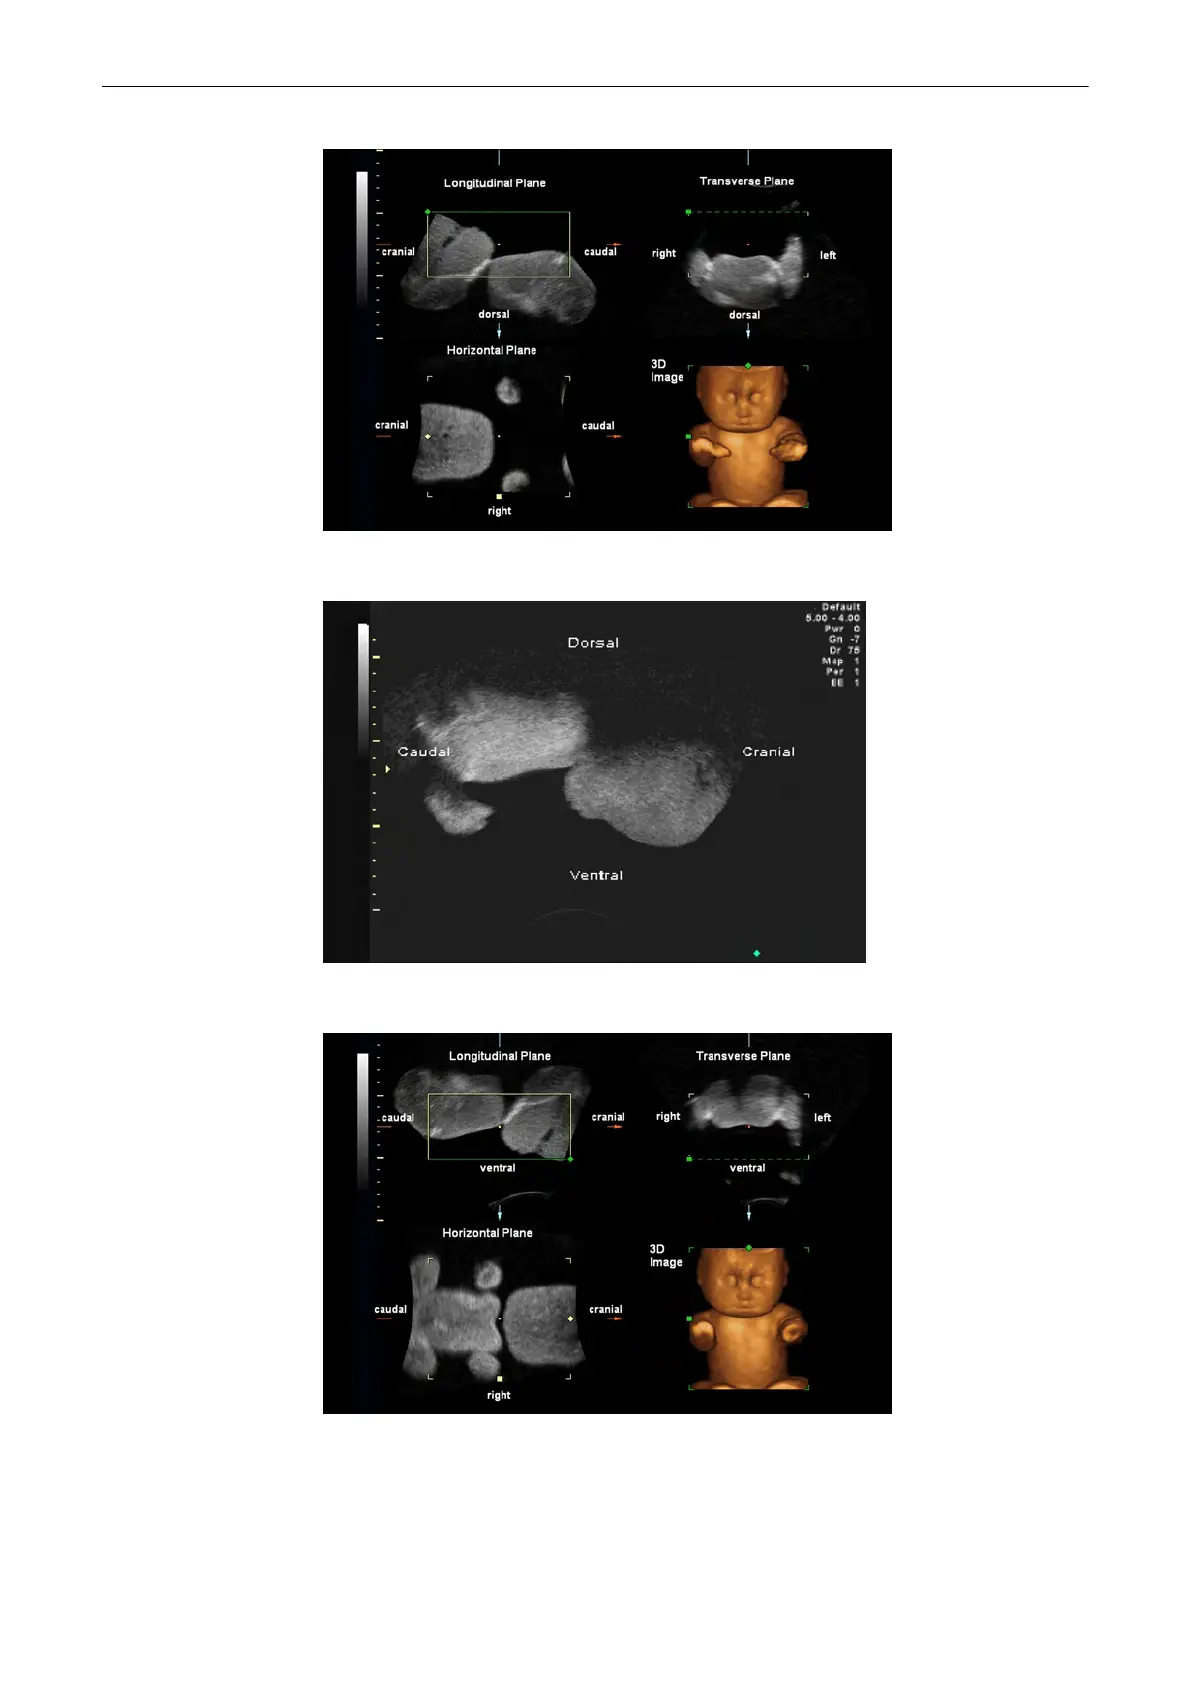

B image orientation: down -> up

Resulting orientation of sectional planes (freeze mode).